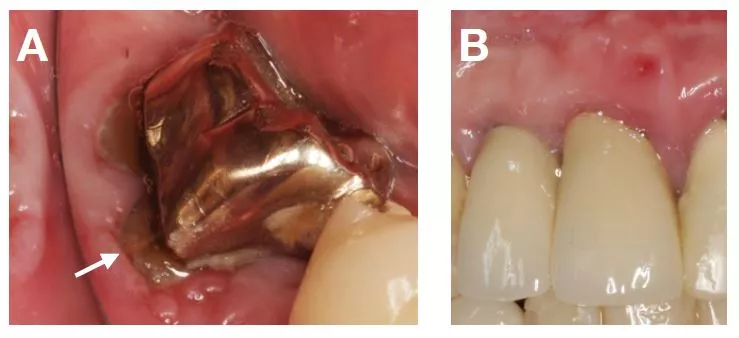

Tabelle 4 fasst alle diagnostizierten orofazialen Erkrankungen zusammen, wobei Anomalien der Zunge (5,1%) und oraler Lichen planus (5,1%) am häufigsten gefunden wurden. Abbildung 2 zeigt klinische Beispiele für relevante orofaziale Erkrankungen.

Tabelle 5 zeigt alle relevanten mechanischen Irritationen, wobei unzureichender Randschluss von FZ (7,7%), unzureichender Halt von HZ (5,0%) oder Schaukeln von HZ bei Druckbelastung (4,3%) am häufigsten festgestellt wurden. Abbildung 3 zeigt klinische Beispiele für relevante mechanische Irritationen durch FZ und HZ.